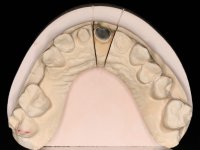

Endodontic treatments were performed and a metalic non screwed intra radicular post was placed on tooth 1.1. An alginate impression was made for laboratory confection of a reinforced acrylic provisional bridge, with teeth 1.1 and 2.2 as abutments and 2.2 as a pontic. After preparation of tooth 1.1 and root preparation of 2.1, the bridge was relined in mouth with self-polymerizable acrylic using a metal post for further retaining the prepared root canal on 2.1. Tooth 2.2 was cut at the gingival level to function as support. In the same session, the impression of the root canal of the 2.1 was made for the laboratory confection of a cast post and core. A double mixture technique with plastic tutor was used after previous canal vaseline with endodontic file and cotton. The provisional bridge was provisionally cemented and the cast post and core was made in the laboratory. Cast post and core cementation was made with resin-reinforced glass ionomer cement and the provisional bridge had to be readjusted to the new situation by removing the post at the site of 2.1. After careful surgical planning, a dental implant was placed, simultaneously with extraction of the root of tooth 2.2. The provisional bridge was placed by resting on the healing screw placed in the implant. The respected osteointegration period was 12 weeks, during which the provisional bridge was relined twice. After complete maturation of hard and soft tissues, definitive impressions were made. The gingival retraction technique was applied with an impregnated retraction cord and impression was performed using double mixture, open tray impression technique. A custom precious metal abutment implant was prepared in the lab, along with 3 metal caps to be used as infrastructures for the metal ceramic crowns. Particular care was taken in the confection of the cervical finishing line of the implant abutment, in order to follow the soft tissues emergence profile. Proof of infrastructures was done in the mouth being evaluated clinically and imagiologically. Collection of color information was done by the ceramist at the office. Ceramic was applied in the laboratory and the finished work was placed in the mouth after approval by the patient. Definitive cementation was made with resin-reinforced glass ionomer cement, and the first crown to be cemented was that of the implant, to facilitate removal of the excess.